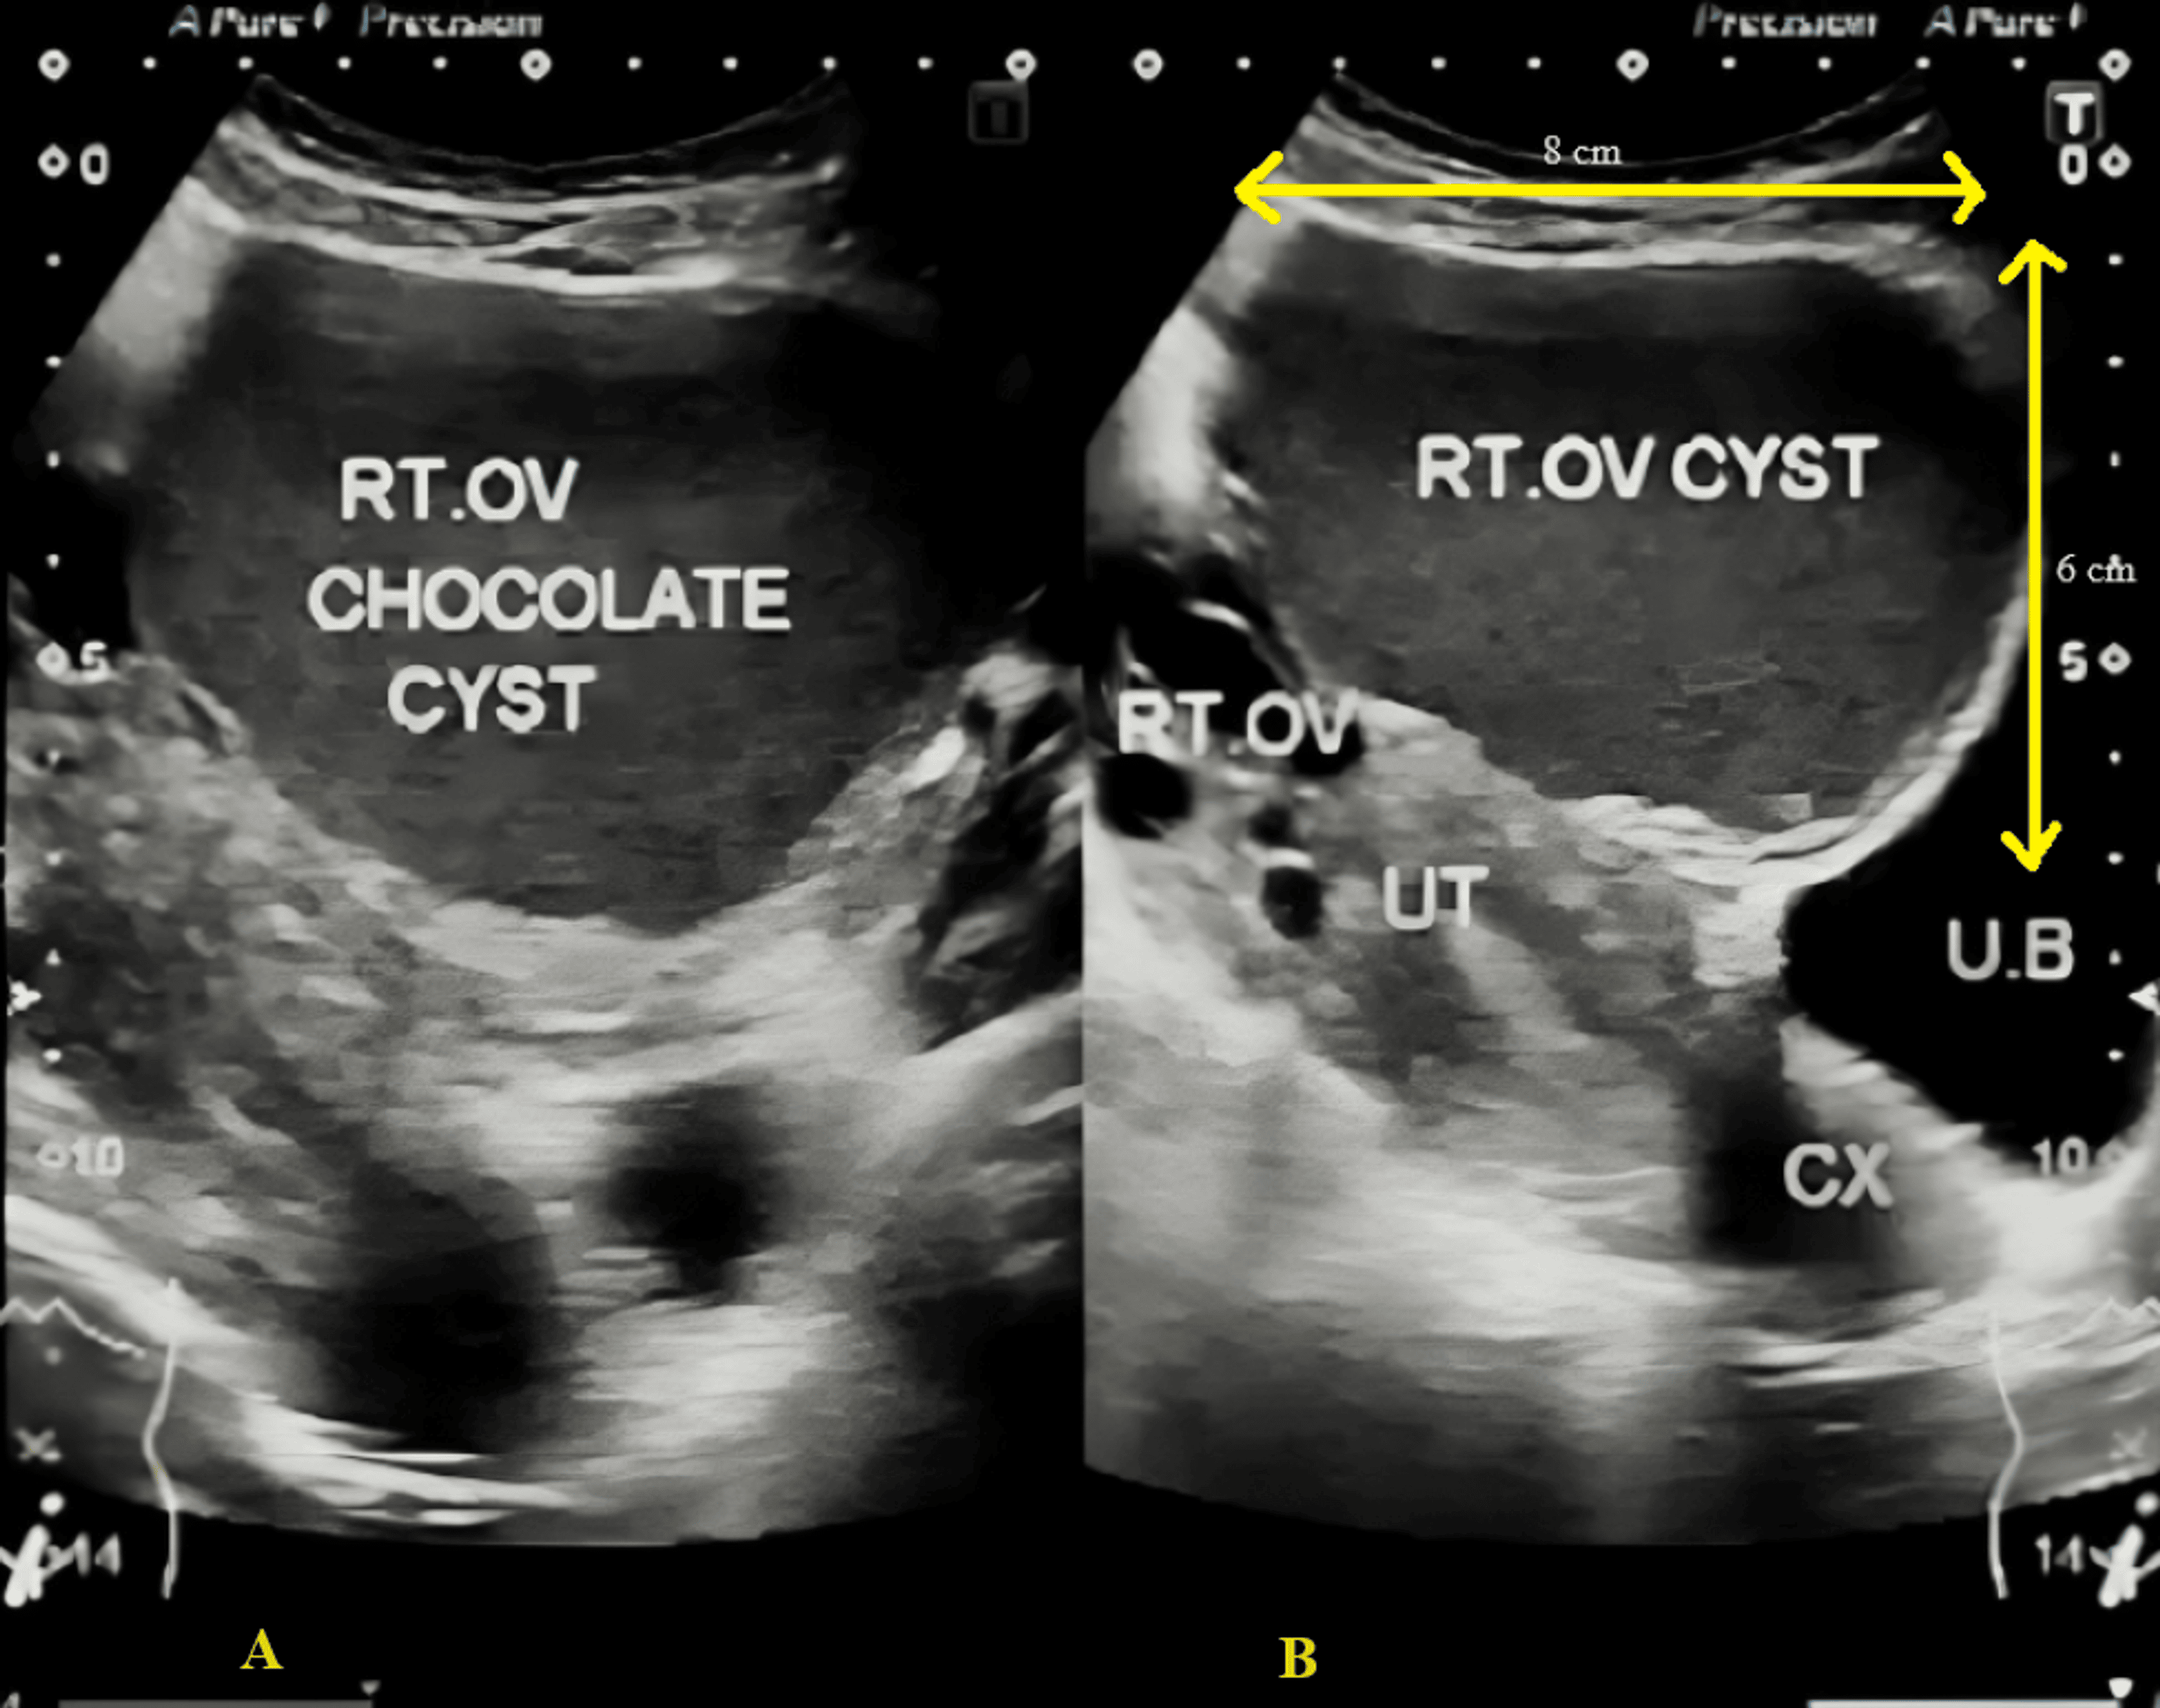

Doppler ultrasound showing multiple cysts on the right (rt) ovary